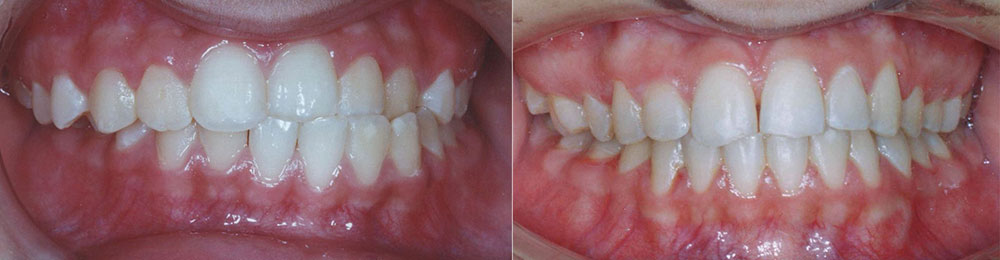

ارتودنسی دندان قبل و بعد، توسط پروفسور جمیلیان

برای دیدن نمونه کارهای ارتودنسی بیشتر می توانید به گالری تصاویر قبل و بعد ارتودنسی مراجعه کنید. در این قسمت تعداد بیشتری از این نمونه کارهای ارتودنسی دندان و فکین را مشاهده خواهید نمود. بسته به ناهنجاری فک و دندان درمان های متفاوتی در نظر گرفته می شود. در اینجا عکس دندان هایی که نیاز به ارتودنسی دارند را مشاهده می کنید. ممکن است بیماری شما نیز شبیه به یکی از این موارد باشد. در این صورت می توانید بهبودی و درمان های موفق را در این قسمت به وضوح مشاهده نمایید.